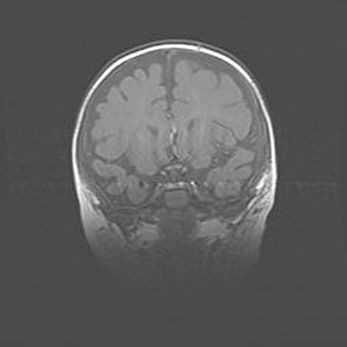

Сообщающаяся гидроцефалия. Кистозная энцефаломаляция головного мозга.

Возраст: 3 месяца 4 дня

Вес: 3100 г

Пол: женский

Окружность головы: 34 см

Срок гестации: 31 неделя

Кистозная энцефаломаляция головного мозга - одна из форм поражения головного мозга в детском возрасте. Характеризуется возникновением множественных и распространённых кист в коре, белом веществе и подкорковых образованиях головного мозга у плодов, новорождённых и детей раннего возраста. Развитие кистозной энцефаломаляции связано с внутриутробной асфиксией и гипотонией, родовой травмой, тромбозом синусов, пороками развития сосудов, инфекциями, сепсисом и другими причинами. Наиболее значимые инфекционные агенты: вирусы простого герпеса, цитомегалии, краснухи, токсоплазмы, энтеробактерии, золотистый стафилококк и другие.